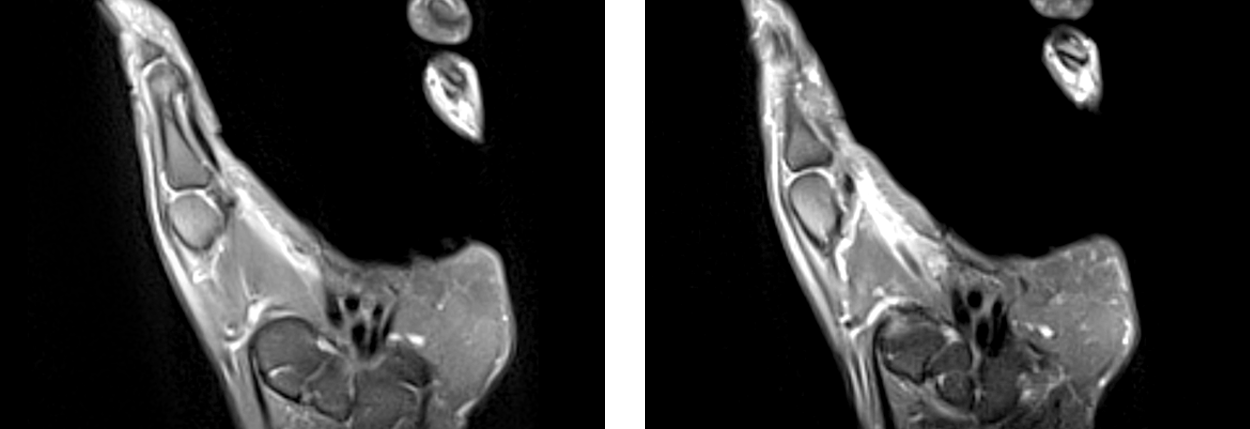

신전건 봉합술

독일 Carl Zeiss 사에서 제조한 미세현미경을 이용하여 미세혈관 같이 육안으로 식별이 어려운 부위를 20배 이상 확대하여 미세한 환부의 수술을 가능하게 합니다.